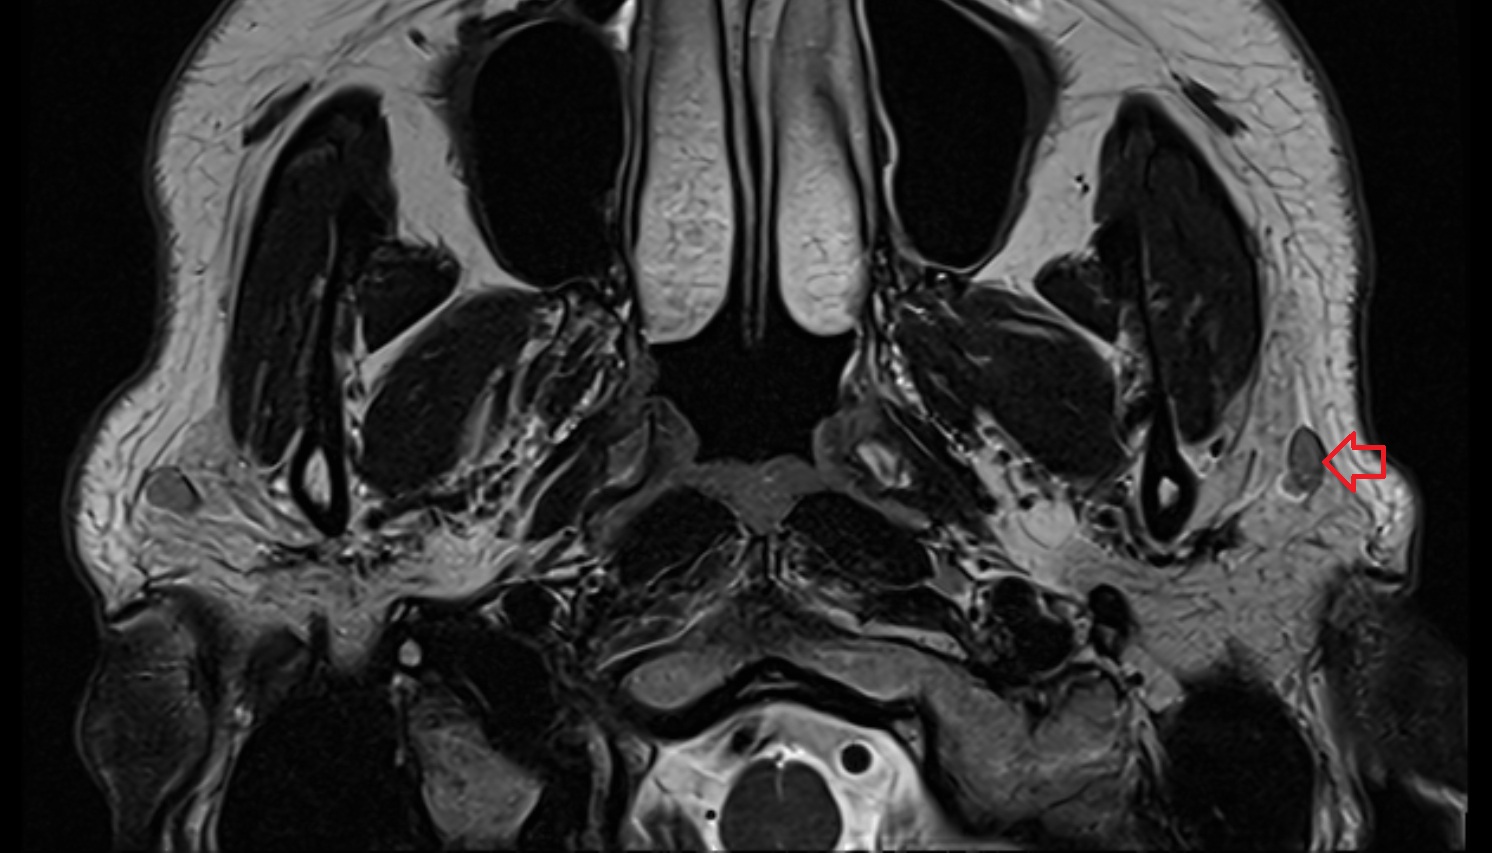

- Temporomandibular joint

- Mandibular condyle

- Mandibular fossa

- Articular disc of temporomandibular joint

- Articular eminence